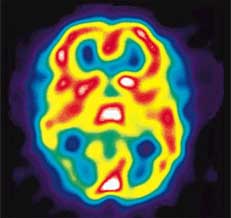

NUCCA can help provide migraine pain relief by alleviating any

misalignments in the vertebrae of the upper cervical spine

(upper neck) caused by trauma such as auto accidents or sports

injuries, as well as poor posture. These misalignments cause

irritation to the nerves traveling between the brain and spinal

cord and to the blood vessels traveling to the head. Nerve

irritation and altered blood flow has been directly associated

with migraines. By correcting the vertebrae in the upper neck,

normal nerve and blood flow is returned and many patients

suffering from migraine headache pain are able to get long term

relief from their symptoms.